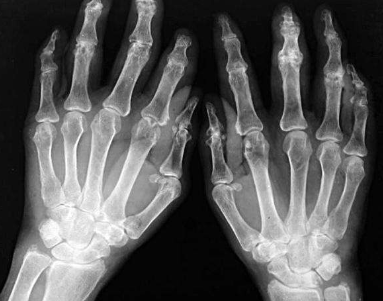

TF16010039 姓名:王先生 性别:男 年龄:41岁

痛风 ①晚期 ②并发症 病史:12年+

治疗后手指关节、脚趾关节痛风石完全清除,血尿酸降至正常水平,手脚各关节痛感消失,关节活动恢复到正常状态。 ??